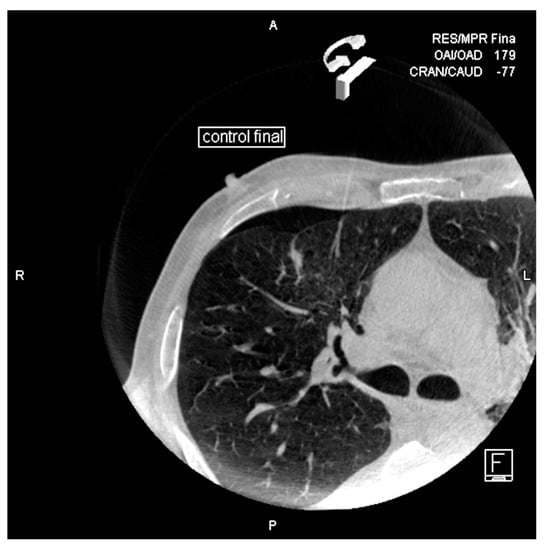

Cone-Beam CT-Guided Lung Biopsies: Results in 94 Patients

- Cone-Beam CT-guided biopsy is a highly accurate and safe technique with a sensitivity of 91.5% and a specificity of 100%.